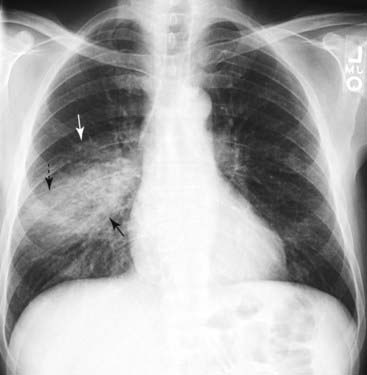

Figure 3-2 Right lower lobe pneumonia.

An area of increased opacification is in the right midlung field (solid black arrow) that has indistinct margins (solid white arrow) characteristic of airspace disease. The minor fissure (dotted black arrow) appears to bisect the disease, locating this pneumonia in the superior segment of the right lower lobe. The right heart border and the right hemidiaphragm are still visible because the disease is not in anatomical contact with either of those structures.